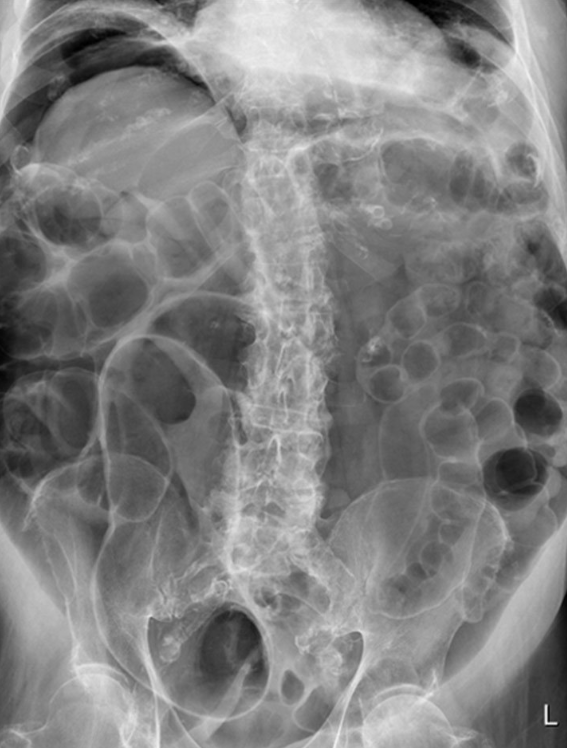

Patient with severe abdominal pain. What does the image show?

What is the likely pathology?

Ascites

Lead pipe colon

Normal gas pattern

Rigler’s/ double wall sign

Thumbprinting

Inflammation of the bowel wall leads to thickening of the haustral folds. This results in the radiological sign of thumbprinting, a characteristic finding in patients with active ulcerative colitis.